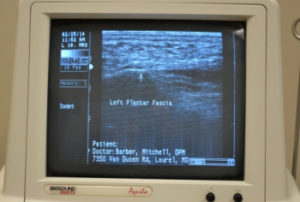

- Digital Ultrasound